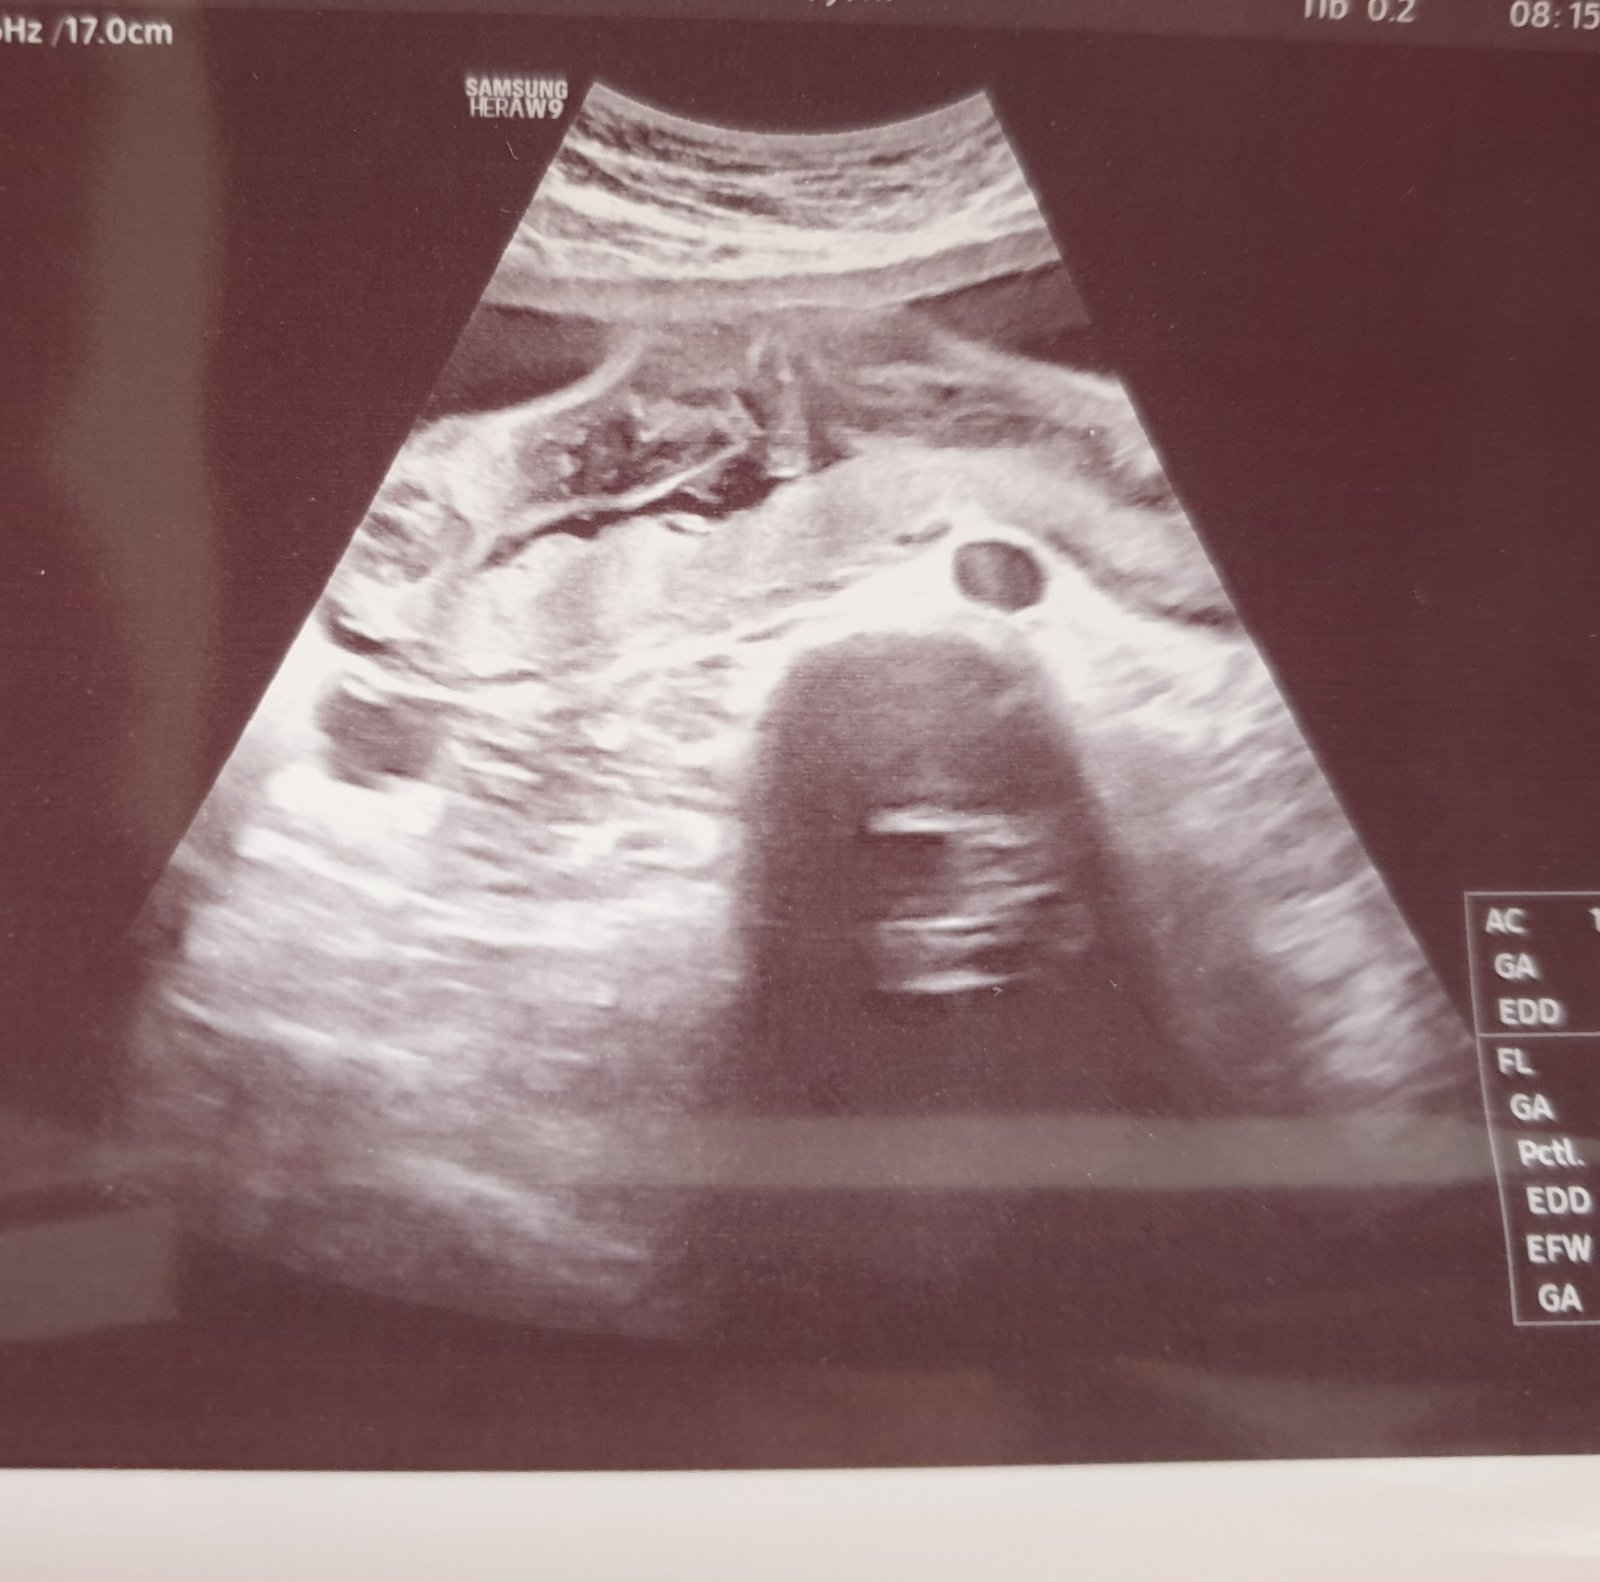

dnes jsme byli na 2. screening, a pak mi doktor odmítl říct pohlaví, protože to prý nikomu neříká, prý se to mají rodiče dozvědět až u porodu. Jenže my patříme k těm, co by to rádi věděli a ani na naléhání mi to neřekl. Udělal nám fotku, a že si to máme poznat sami.

Prosím, poznáte podle fotky Vy, zda čekáme chlapečka nebo holčičku?

bohužel, z této fotky to posoudit nelze.🙂